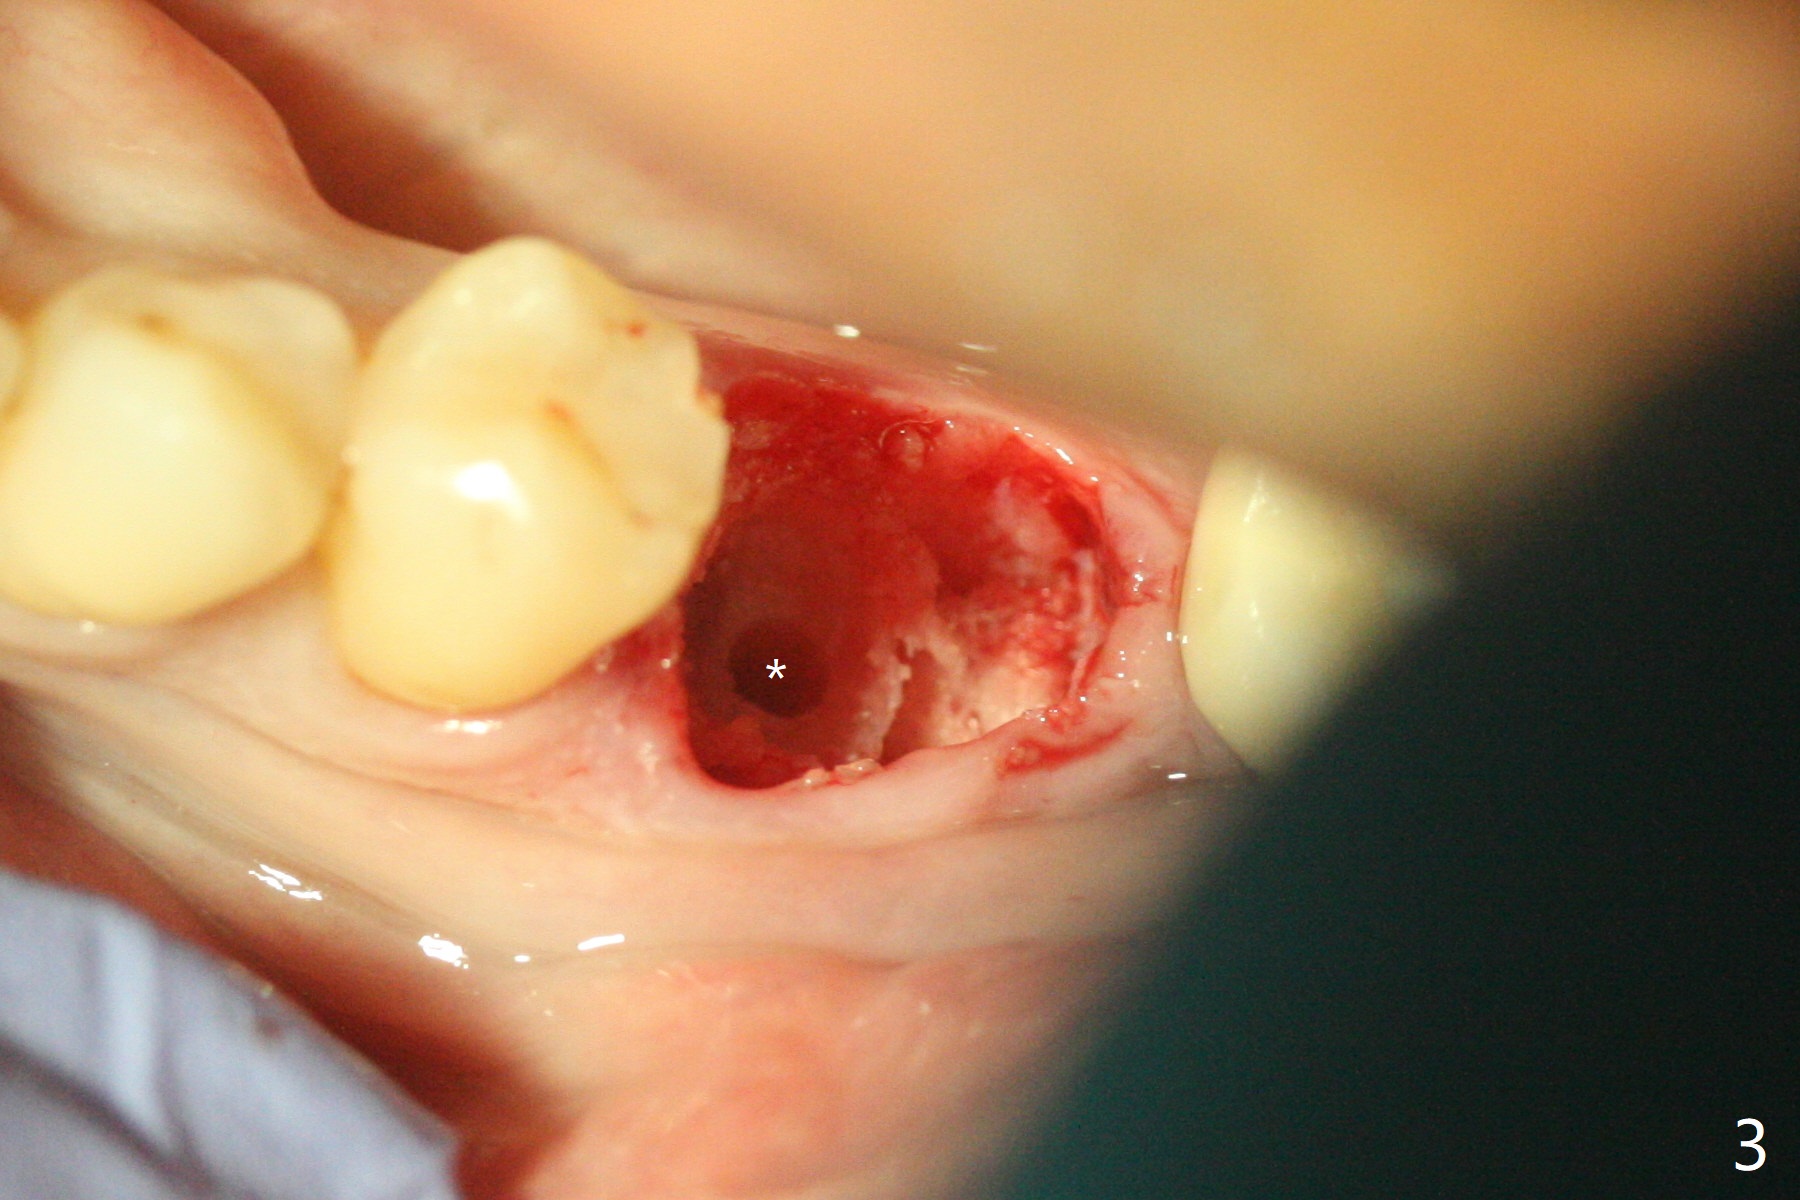

Venopuncture is conducted (Fig.1) for PRF and sticky bone (cortical chip and .5 cc ß-TCP). After use of proximators at #19, cowhorn forceps are applied, resulting in metal crown dislodgement. Since there is distal bone loss, distal socket sheath is contemplated. The tooth is sectioned. When an elevator is inserted between the roots, the distal root is loosened first. The 2 roots are removed, revealing a rounded end septum (Fig.2 S) and a larger distal socket. To avoid osteotomy deviation over the septum, a 12 mm bone trimmer is used, followed by point drill (Fig.3 *). But the lower half of the implant is deviated mesial (Fig.4) with decreased torque (~ 10 Ncm). To overcome this misfortune, the roots should not be removed until osteotomy is finished. Dual zones of bone graft is conducted. Sticky bone is placed until the plateau of the implant with a healing screw in place (Fig.4 * (bone zone)). After placement of a pair abutment, the same bone graft is packed until the margin of the abutment (Fig.5 * (soft tissue zone)). An immediate provisional is fabricated to close the socket with a piece of PRF as well. Fig.6-11 explains why the lower half of the implant deviates to the mesial socket, while Fig.12-16 illustrates how to prevent the deviation. After extraction of #19 (Fig.6,7), the crest of the septum is flattened (Fig.8 arrowhead) to prevent the initial deviation (Fig.9 red line). When a drill reaches a space (a socket, mesial in this case), the drill is deflected to the least resistant area (Fig.10 a bent red line), leading to the implant deviation apically (Fig.11 green). To prevent the apical deviation, therefore, the roots of the affected tooth is temporarily not removed (Fig.12). The osteotomy should not deviates with surgical guide because of similar density between the tooth and the bone (Fig.13). When the osteotomy is finished (Fig.14), the roots are extracted (Fig.15). The implant to be placed should not have deviation (Fig.16 green). The papillae are maintained by the immediate provisional 11 days postop (Fig.17). The incompletely seated abutment at #18 (Fig.5 <) is reseated completely 6 months postop (Fig.18). Crestal bone forms distal to #19 implant. There is no bone loss 4 months and 3 years 1 month post cementation at #19 and 18, respectively (Fig.19,20).